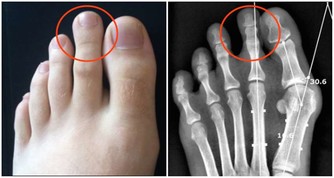

國慶假期前,陳先生去做了一次身體檢查,結果出來后他傻了眼:肝內總脂肪量佔到肝重的10%,輕度脂肪肝。

據統計,約有22%的素食者會得脂肪肝,而這些人也大多是正常體型。劉曉光醫師稱,人體中所需要的能量主要來自三大營養物質,脂肪、蛋白質和碳水化合物。像陳先生這種純素食者,不吃魚肉蛋等營養物質,也就是少了動物蛋白質和脂肪來源,人體的白蛋白合成減少,就需要分解脂肪組織來維持營養均衡,大量的脂肪酸從脂肪組織中釋放進入肝臟后,而這種脂肪在肝臟中不易被分解,若不能及時排出,肝臟中的脂肪堆積過多,長期以往,就形成了脂肪肝。